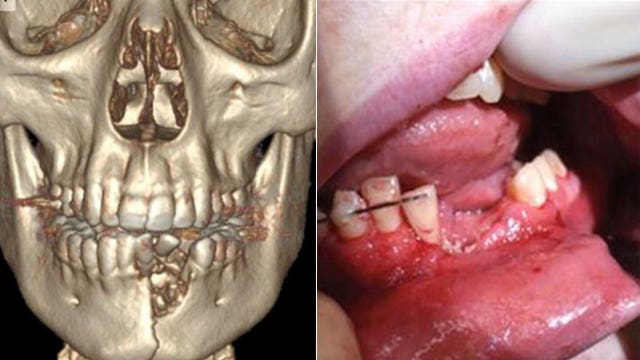

Vape pen explodes, shattering teenager's jaw and knocking out some teeth

A vape pen exploded in a teenager's mouth, causing injuries so severe a pediatric surgeon who helped him said it looked similar to a "gunshot wound."